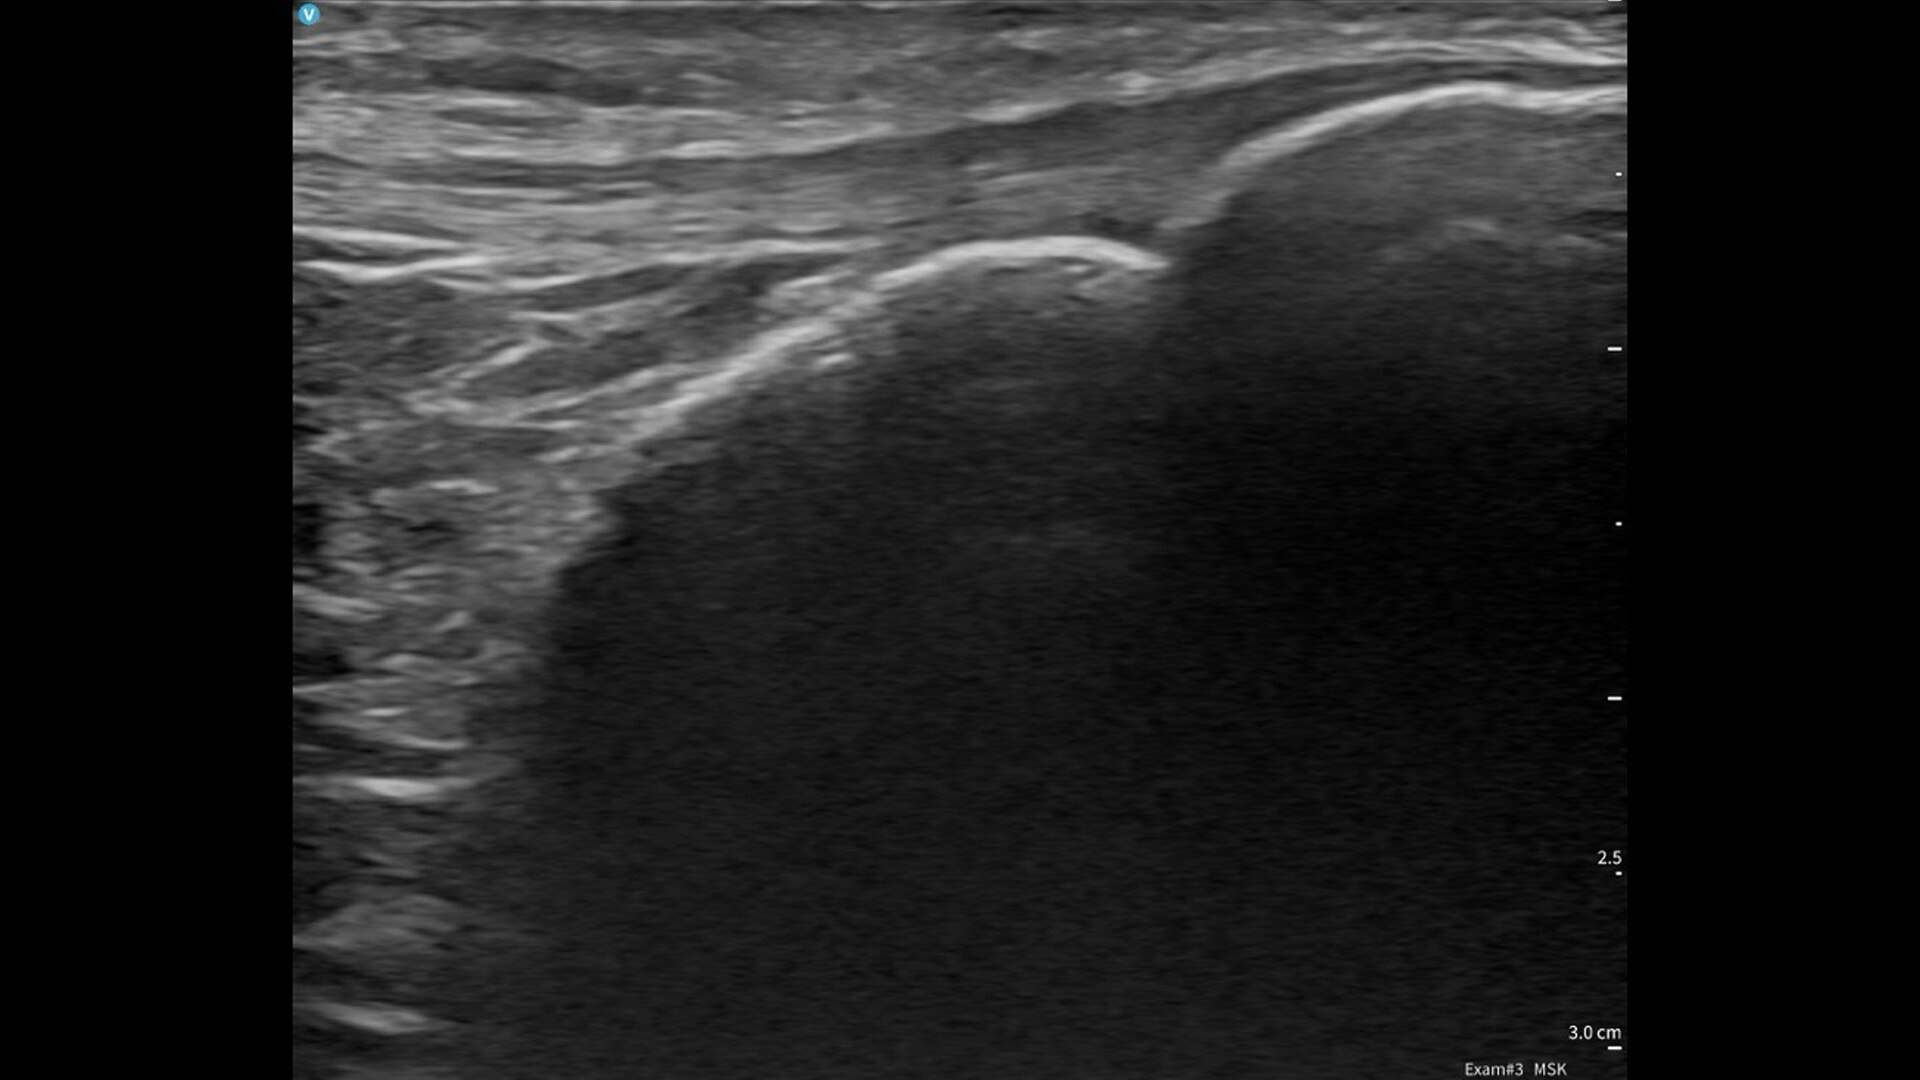

Vscan Air CL offers wireless freedom and maximum portability. One device delivers the value of two: the curved array transducer is ideal for abdominal imaging, obstetric assessments and more, and the linear array is ideal for vascular, MSK, lungs and more. Complete both shallow and deep scans with one device without compromising image quality.

Quality imaging capabilities for multiple clinical healthcare applications.

Ideal for OB/GYN, musculoskeletal, abdominal, lungs, and more. Complete both shallow and deep ultrasound scans with one probe without compromising image quality.

Image quality you can be confident in

Vscan Air leverages the power of our proprietary technology, SignalMaxᵀᴹ, to uniquely combine the miniaturization of hardware with the high transmit power of piezo electric crystals into a beautifully engineered small lightweight footprint for outstanding image quality. We take image quality one step further with our High-Definition Speckle Reduction Imaging (HD-SRI) for a boost in image quality that enhances details of images even more.

Key features for all users and specialties

Built for both new and experienced handheld ultrasound users with basic and advanced assessments in mind. Now including: B-mode; Color Doppler; PW Doppler; M-mode; and OB measurements.